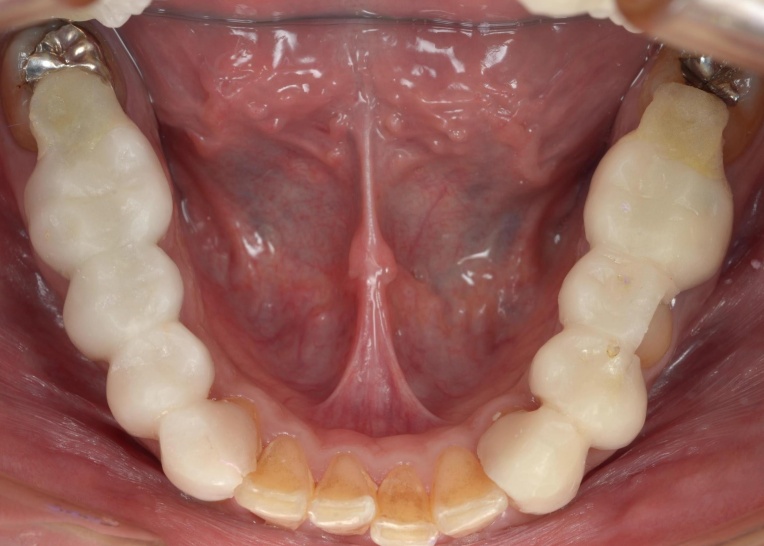

治療前

拝見したところ、抜歯矯正によって歯間に不要な隙間が生まれ、歯列全体のバランスが崩れています。

また、矯正力の強さや力をかける方向が適切ではなかったおそれがあり、歯根が短くなる重度の「歯根吸収」が複数の歯に見られました。歯根が短くなると歯を支える力が弱くなるため、歯が揺れやすくなります。

これらの問題が重なった結果、噛み合わせが不安定になって顎の位置にもずれが生じ、頭痛や首のこりなどの症状につながったと考えられました。